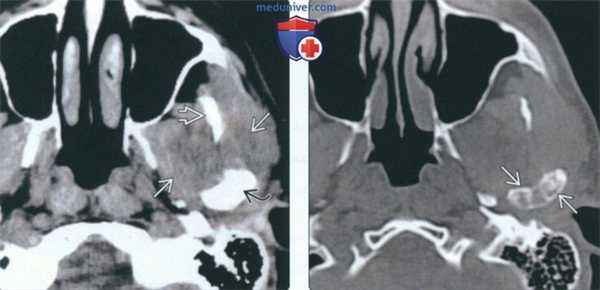

(Слева) КТ с КУ, аксиальная проекция. Злокачественная фиброзная гистиоцитома жевательного пространства и нижней челюсти. Солидная опухоль, которая умеренно накапливает контраст, располагается в правом жевательном пространстве и разрушает нижнюю челюсть, в том числе ее ветвь и тело. Жевательное пространство представляет собой глубокую область лица, в которой может возникать саркома.

(Справа) КТ с КУ, аксиальная проекция, тот же пациент. Солидная опухоль, умеренно накапливающая контраст, разрушает значительную часть нижней челюсти.

(Слева) На аксиальной КТ с КУ в жевательном пространстве справа визуализируется злокачественная фиброзная гистиоцитома нижней челюсти в виде минимально контрастирующегося солидного объемного образования, разрушающего ветвь и тело нижней челюсти. Жевательное пространство является известным местом возникновения сарком глубоких областей ли ца.

(Справа) На аксиальной КТ с КУ у этого же пациента визуализируется опухоль в жевательном пространстве справа, приводящая к обширной деструкции нижней челюсти. Обратите внимание на асимметрию лица на стороне поражения.